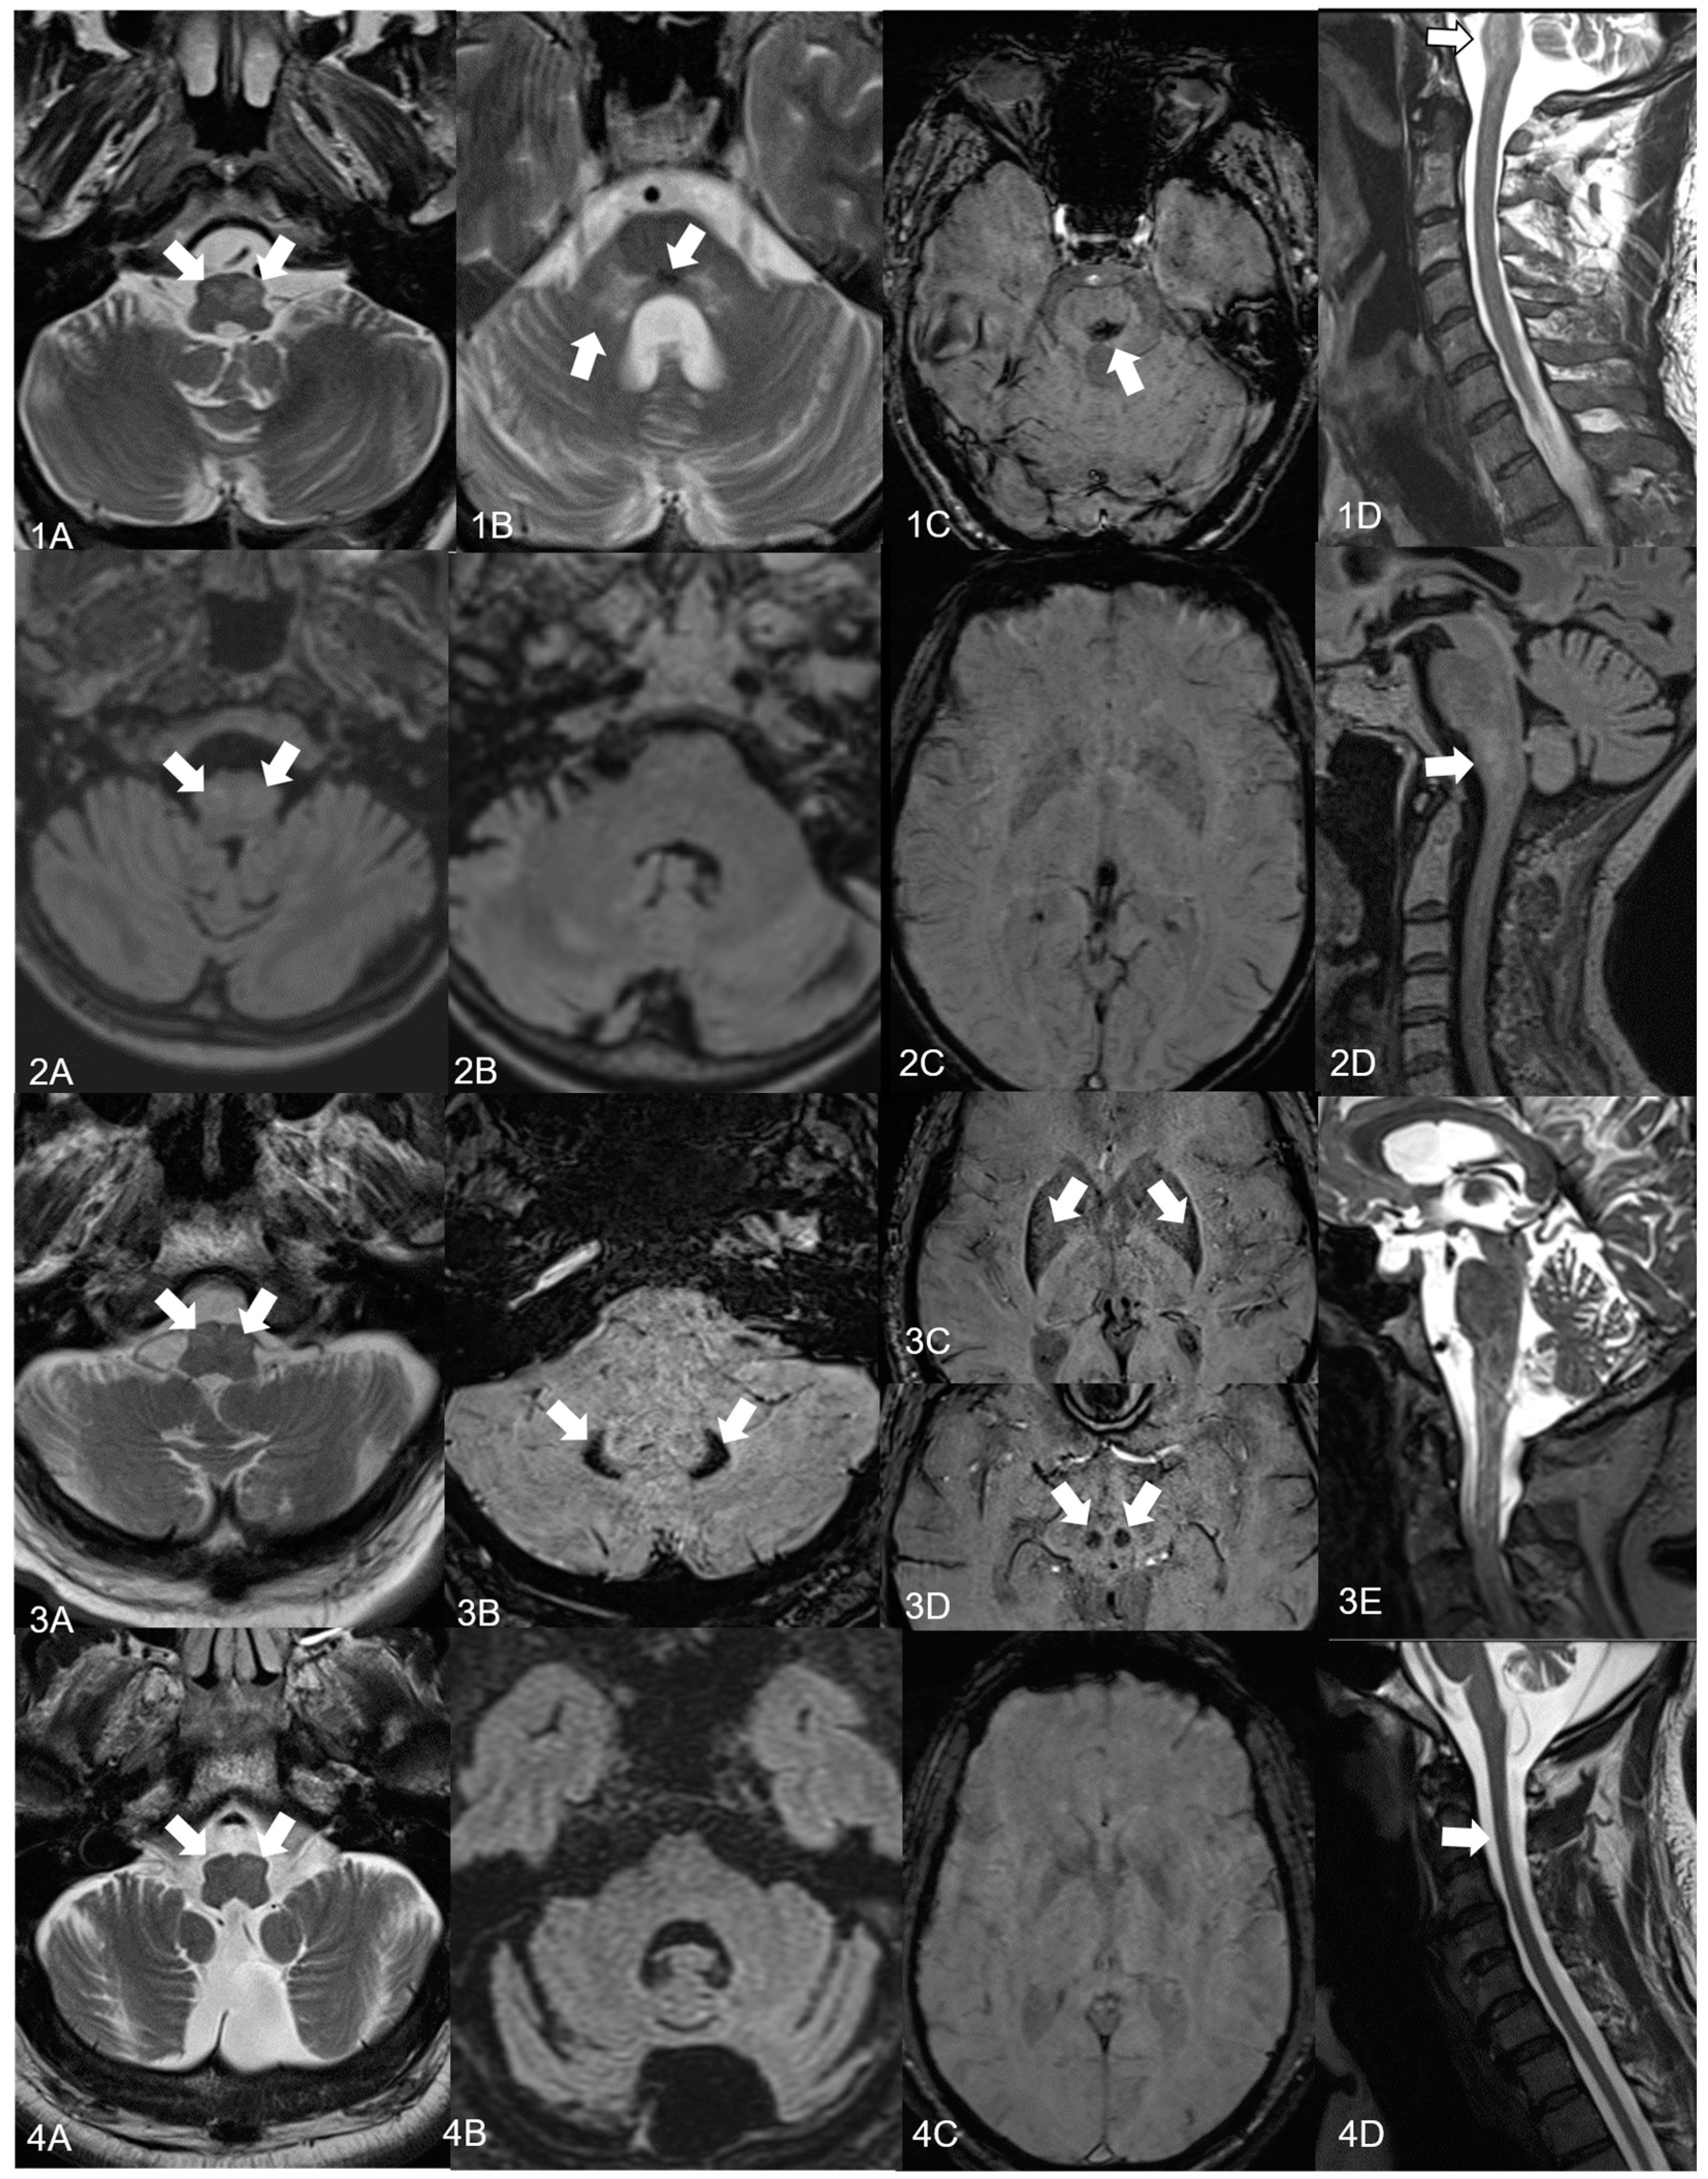

| MRI cerebellar atrophy brainstem atrophy supratentorial atrophy HOD left/right further findings | + − − +/+ (sequential) SWI lesion in dorsomedial pons T2 signal alterations of the cerebellar peduncles | + − − +/+ | + − + +/+ susceptibility artefacts in the posterior and lateral putamen, red nucleus, dentate nucleus on SWI | + + + +/+ (sequential) |